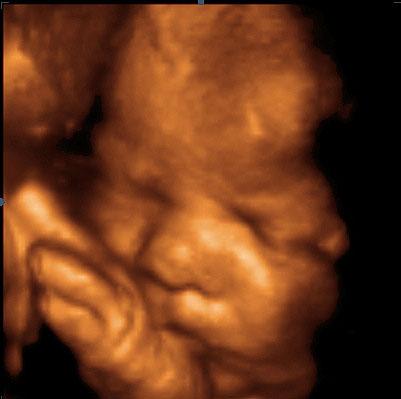

Ve 33. týdnu těhotenství měří plod zhruba 44 cm. Pro určení délky plodu se nyní používá součet délky hlavičky, trupu a nohou. Váha plodu je nyní zhruba 1900 g.

Plod si dumlá paleček.